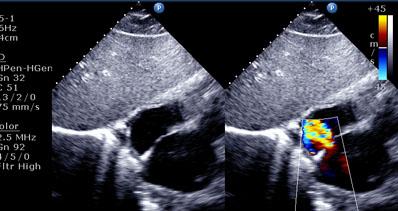

The 2010 Physician Fee Schedule released Friday by CMS will reduce payments to non-hospital practices by 48 percent for pelvis CT, by 46 percent for MRI of the chest-spine, and by 27 percent for cardiovascular-related services. Cuts to cardiology services could impact up to two-thirds of cardiovascular patients as practices are forced to shut their doors.